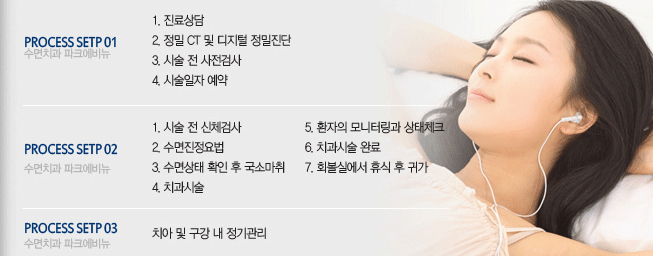

이제 임플란트 수술도 주무시면서 진행되는 수면마취로 안아픈 임플란트 수술이 가능합니다

따라서 임플란트 수술시 느끼는 통증이나 두려움이 없이 편하게 임플란트수술을 받을수 있습니다